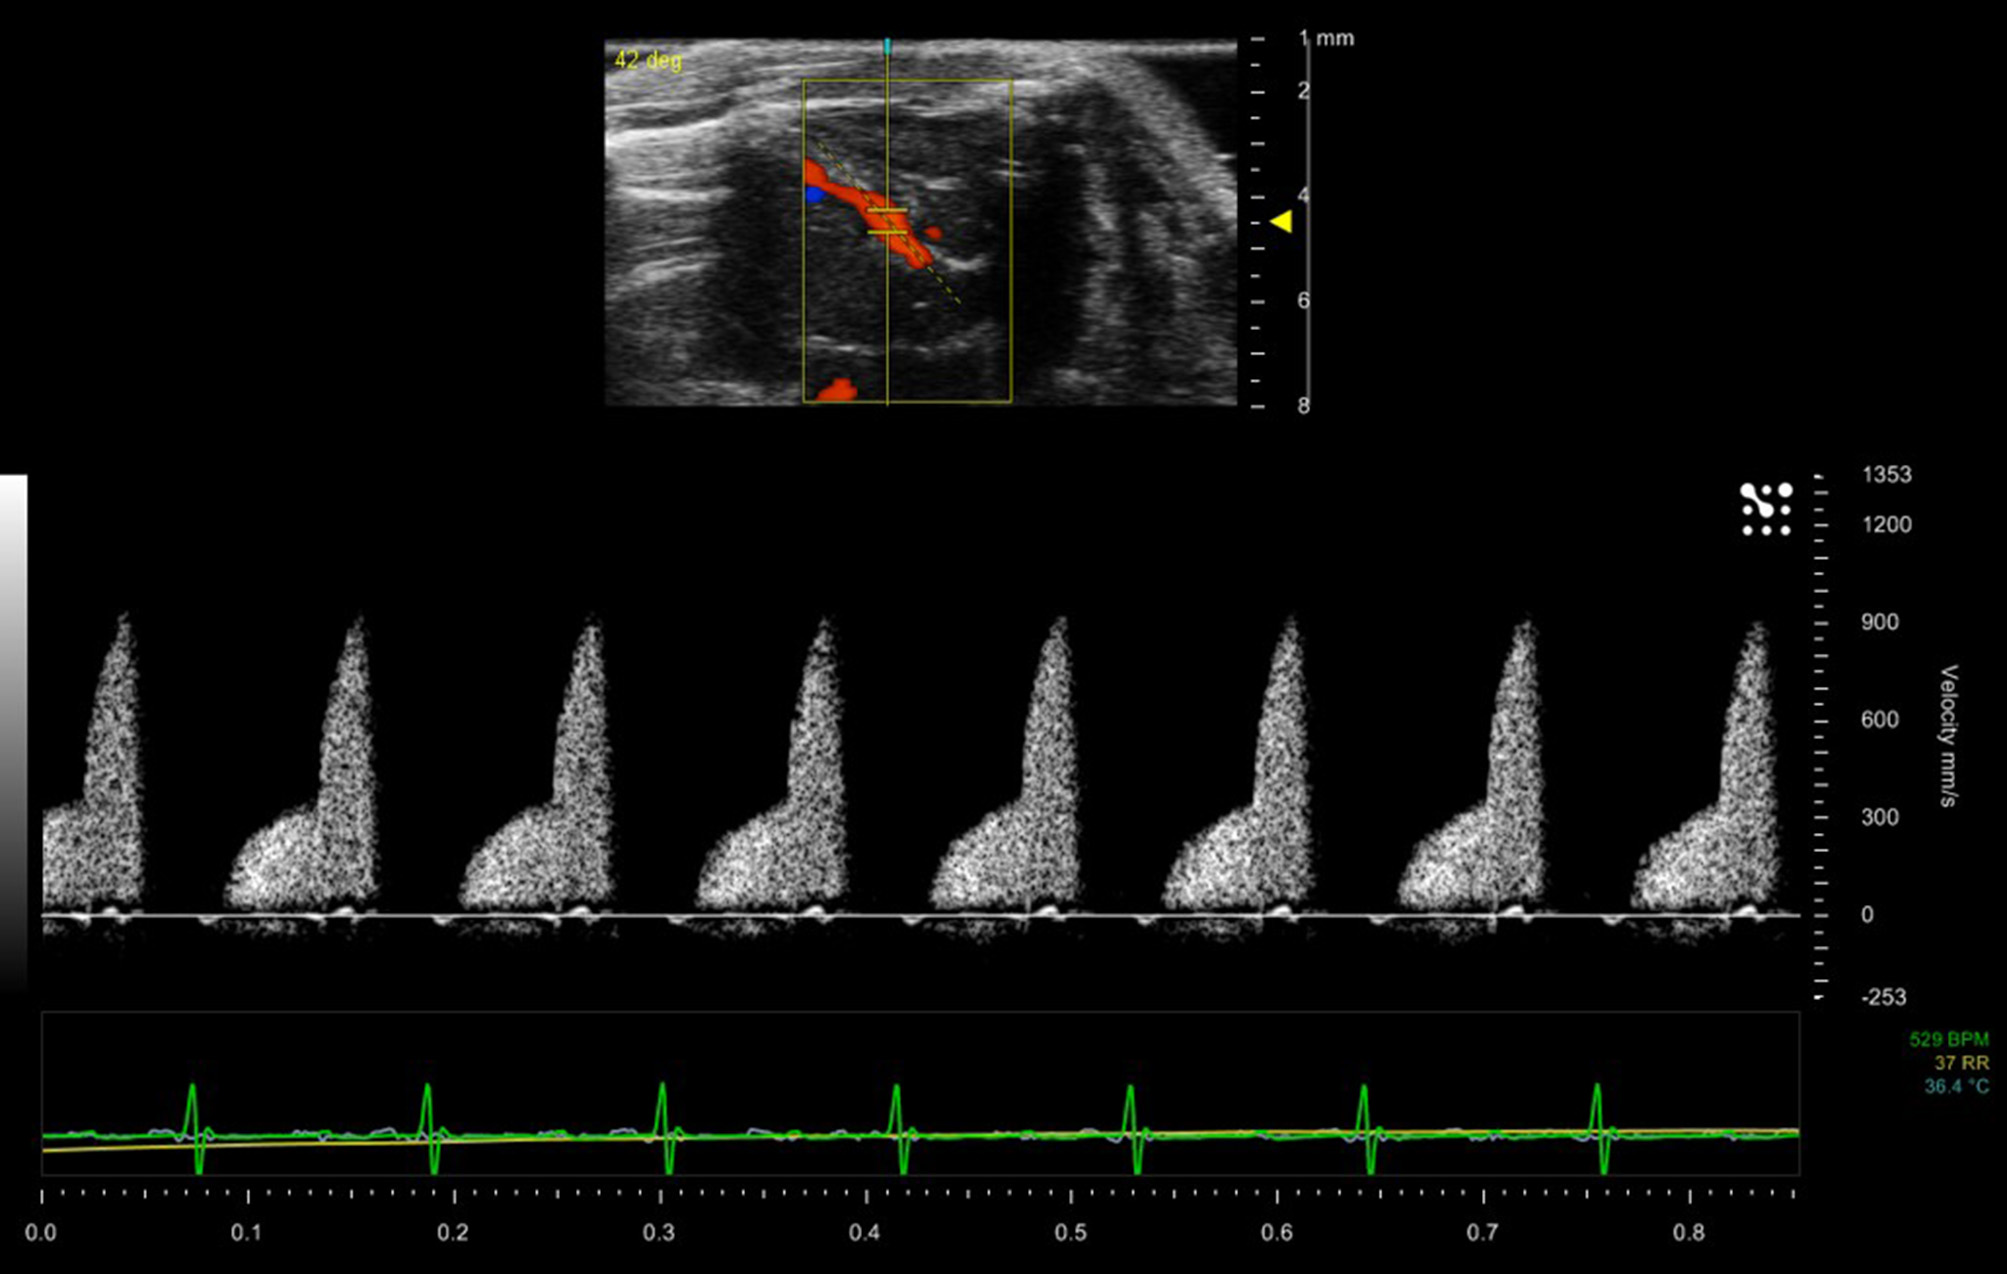

Color Doppler is used in adult rodent echocardiography for the rapid assessment of blood flow within the chambers and specifically across valves. Constriction of valves can result in jetting which can be visualized as rapid flashes of color across the valves during contraction of chambers. This enables easier localization of the spectral Doppler sample volume within the jet to measure maximal velocities for assessment of constriction of valves. Color Doppler can also be used to localize small vessels. Figure 11 shows a duplex image (color and spectral Doppler) where color Doppler has being used to localize and identify the left anterior coronary artery and spectral Doppler enabling measurement of the velocities within the artery.

FIGURE 11

www.frontiersin.org

Figure 11. Blood flow within the left anterior descending coronary artery of a mouse model. Maximum velocity within the artery is 900 mm/sec.